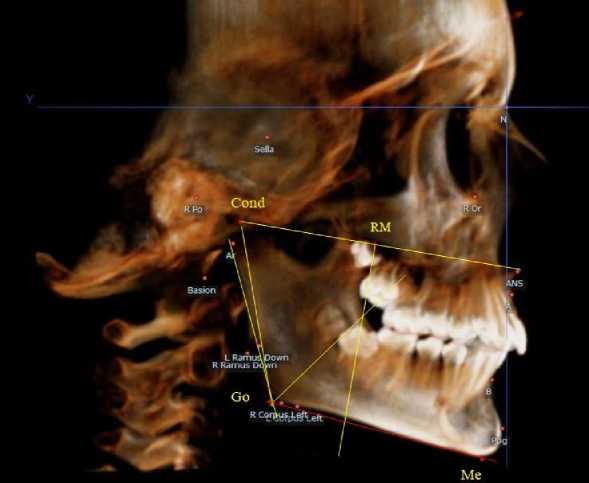

Основу анализа телерентгенограмм составляла кондиллярно-спинальная линия, соединяю- щая верхнюю точку суставной головки с передней носовой остью (Cond-SNA). На середину указанной линии ставили точечный ориентир (RM), от которого вниз проводили перпендикуляр, который, так же, как и на ортопантомограмме, ограничивал ретро молярную область (рис. 2).

Рис. 2. Анализ боковой телерентгенограммы (а) и 3D-модели (б) в периоде сменного прикуса

Стресс-осью для оценки положения нижнего дистального зуба (или зачатка зуба) служила биссектриса кондилярно-гониально-ментального угла ( Cond-Go-Ме ), в отличие от аналогичной оси ортопантомограммы.

При анализе боковых телерентгенограмм и трехмерной модели установлено, что положение зубов и челюстей относительно реперных линий было близким по значениям, полученным при анализе ортопантомограмм.

На середину суставной горизонтальной линии Cond-SNA ставили точечный ориентир ( RM ), от которого вниз проводили перпендикуляр, который, так же, как и на ортопантомограмме, ограничивал ретромолярную область. Зачаток первого верхнего постоянного моляра, как правило, располагался впереди ретромолярной вертикали.

Биссектриса угла Cond-Go-Ме (стресс-ось), так же, как и на ортопантомограмме, располагались позади от формирующихся зачатков первых постоянных моляров нижней челюсти (рис. 4).

Рис. 4. Особенности боковой телерентгенограммы (а) и 3D-модели (б) ребенка 4 лет в периоде прикуса молочных зубов